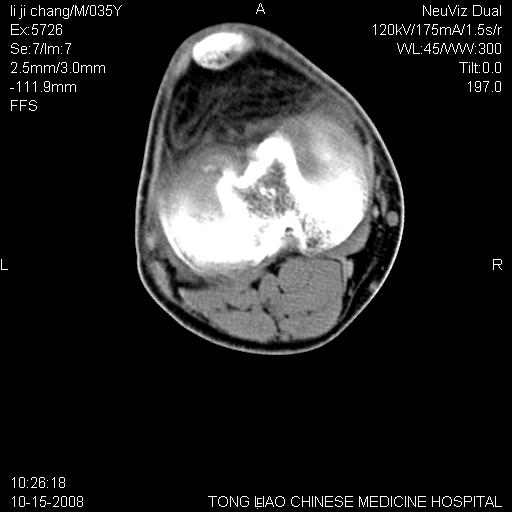

男,35岁,骨科诊断骨性关节炎。继往使用过激素,现股骨头坏死。膝关节病变,请会诊

一元论-----亦考虑为坏死

支持考虑无菌坏死

支持无菌坏死伴退行性骨关节病.

剥脱性骨软骨炎:是一种关节下软骨及软骨下骨缺血性坏死。

支持 无菌性坏死伴退行性骨关节病。